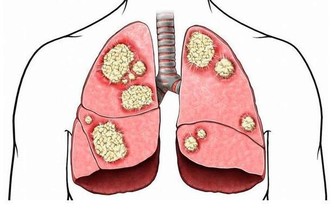

紅莧菜具有解毒清熱、補血止血、抗菌止瀉、消炎消腫、通利小便等功效;

莧菜平衡酸鹼值,補血又使痛風消。莧菜有紅莧、白莧,應該大量推廣。

莧科植物含有最豐富的生物鹼,所有現代人吃的肉和很多食物,會轉化成酸性物質。

尿酸痛風的人,可以每天吃一碗莧菜湯,或像我們客家人用莧菜煮麵線,但是不要放吻仔魚。